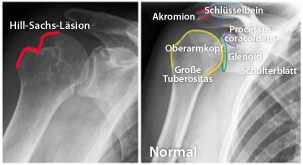

- Eine Schädigung des Oberarmkopfes, die als Hill-Sachs-Läsion bezeichnet wird (3). Durch eine Verschiebung des Oberarmknochens nach vorne kommt es zu einer Eindellung im hinteren und äußeren Bereich des Oberarmknochens.